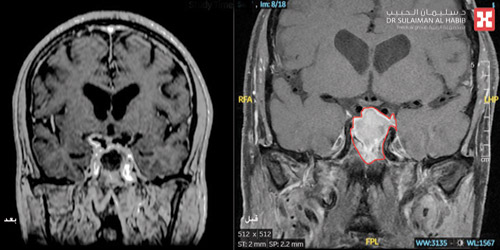

وأفاد بأنه بناء على وضع المريض الصحي فقد تم تحويله إلى وحدة العناية المركزة، وأجريت له مجموعة من الفحوصات والتحاليل كشفت عن وجود «ورم غدي نخامي» متمركز في قاع الجمجمة بطول 3 سم ونصف ضاغط على الغدة النخامية والعصب البصري من الجهتين؛ الأمر الذي أثر على حركة العينين، وكذلك المنطقة الجانبية (الجيب الكهفي الدماغي) الذي يحوي الشرايين الرئيسية المغذية للدماغ، كما بينت نتائج التحاليل أن القصور الشديد في عمل الغدة النخامية نتج عنه خلل بنسبة صوديوم الدم، بالإضافة إلى حدوث اضطرابات في أملاح الدم وكذلك نقص في نسب الهرمونات بالجسم وخاصة هرمون الكورتيزون.

وقال الدكتور بهاء إنه تم تكوين فريق طبي من استشاري الأنف والأذن والحنجرة والغدد الصماء والعناية المركزة والتخدير، وعقب دراستهم لمعطيات النتائج أوصوا بضرورة التدخل الجراحي السريع، وذلك للحيلولة دون إصابة المريض بمزيد من الأعراض التي قد تؤثر على حياته. وتم البدء في إعطاء المريض الأدوية لإعادة نسب الهرمونات إلى طبيعتها، وبعدها أجريت له عملية جراحية دقيقة استغرقت 6 ساعات متواصلة تحت التخدير العام، واستخدم الفريق تقنيات المنظار والملاحة العصبية، وكذلك تطبيق تكنيك جراحي يُعرف باسم «الأيادي الأربعة» لتفادي عمل فتح جراحي بالجمجمة، وتم الوصول لمكان الورم عبر فتحة الأنف وتحريره واستئصاله بالكامل - ولله الحمد - دون أية مضاعفات مع الحفاظ على لوظائف الغدة النخامية، ونقل بعدها المريض إلى العناية المركزة.